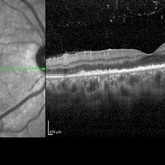

Posterior Placoid Chorioretinitis Posterior Placoid ChorioretinitisMar 9 2025 by Oscar Francisco Miranda, MD A 36-year-old male with bilateral visual loss of 3 months' duration, with no relevant medical history on inquiry. A round-shaped lesion with well-defined borders and a yellowish-white color is observed in the macula of both eyes, accompanied by vitreous cellularity. The macular OCT shows a dentate RPE. The VDRL, FTA-ABS, and HIV tests were positive. Photographer: Oscar Francisco Miranda-Gómez Imaging device: Heidelberg Spectralis Condition/keywords: acute syphilitic posterior placoid chorioretinitis, OCT, Ocular syphilis